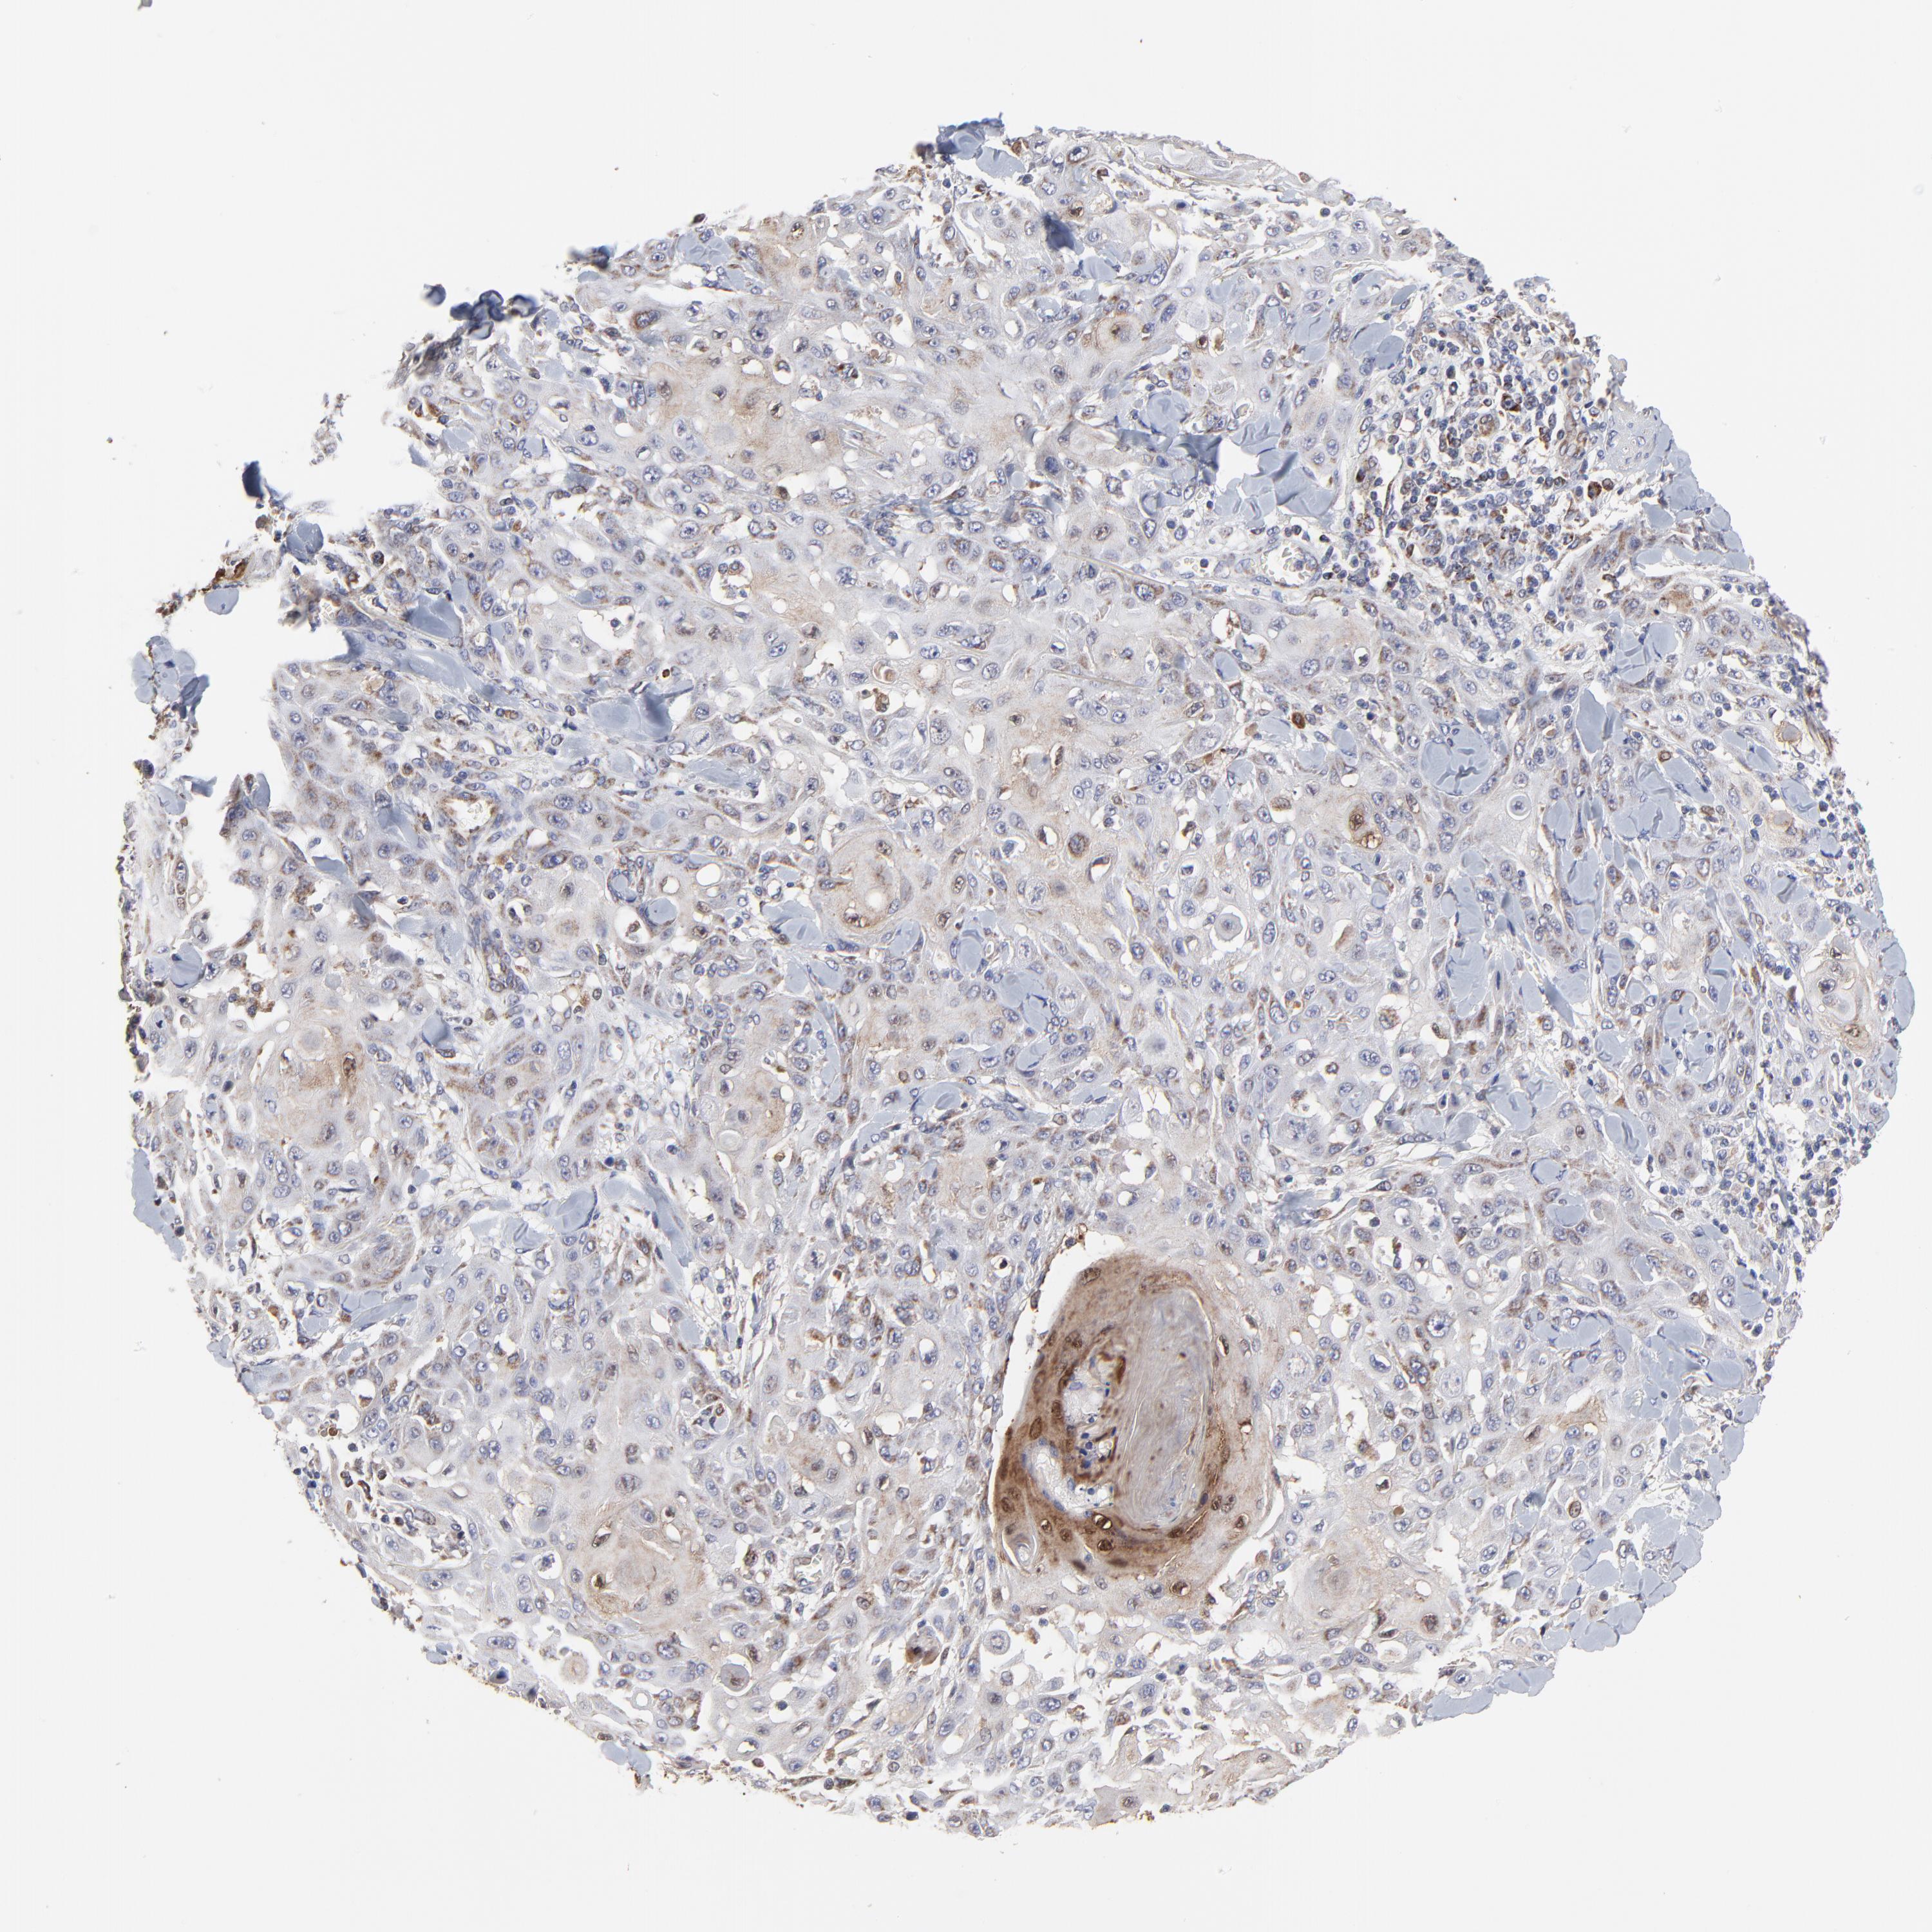

CANCER SKIN CANCER Show tissue menu

Basal cell and squamous cell cancer

SKIN CANCER - Protein expressioni

A mouse-over function shows sample information and annotation data. Click on an image to view it in a full screen mode. Samples can be filtered based on level of antibody staining by selecting one or several of the following categories: high, medium, low and not detected. The assay and annotation is described here.

Each image is clickable and will lead to virtual microscopy that enables deeper exploration of all samples and also displays staining intensity scores, fraction scores and subcellular localization as well as patient and tissue information for each sample.

Antibody HPA003251

Staining

High

Medium

Low

Not detected

Intensity

Strong

Moderate

Weak

Negative

Quantity

>75%

75%-25%

<25%

None

Location

Nuclear

Cytoplasmic/membranous

Cytoplasmic/membranous,nuclear

Squamous cell carcinoma, NOS

Basal cell carcinoma